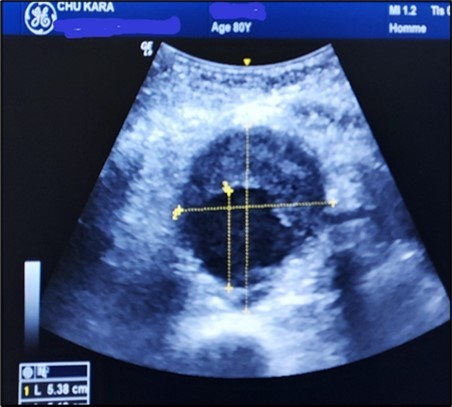

Aneurysms were thrombosed in 24 patients (75%). (Figure 3) and (Figure 4) Arterial occlusion was found in 11 patients (73.33%) and significant stenosis in 4 patients (36.36%). (Table 7).

The aneurysms had extensions to other arteries in 21 patients (65.63%) distributed as follows: superior mesenteric artery (11.76%) (Figure 3) and (Figure 4), celiac trunk (14.23%), iliac arteries (57.14%) femoral arteries (19.05%). (Figure 5) and (Figure 6)

Figure 5.Subrenal AAA of 5.38 cm partially thrombosed in half in an 80-year-old subject (CHU-Kara).